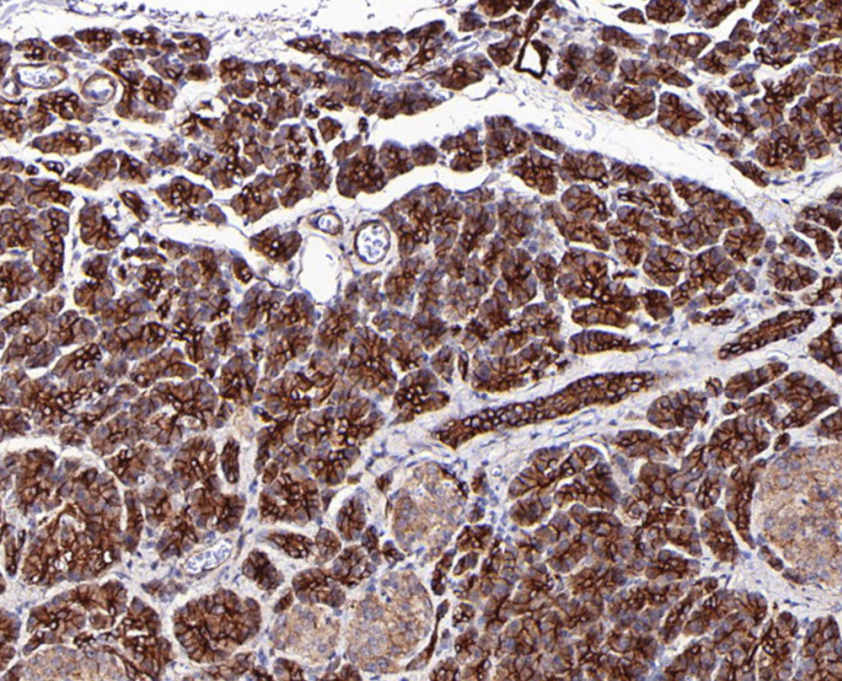

Cellular localization: cell membrane

Tissue: paraffin section

Claudin4 is a tight junction protein, one of the key proteins affecting the function of intercellular tight junctions. It is overexpressed in epithelial tumors such as pancreatic, breast, ovarian, prostate, bladder, and endometrial cancers, which on the one hand reduces the invasive and metastatic ability of tumor cells, and on the other hand, claudin-4 high-expressing tumors may be a potential target for therapeutic approaches of CPE.

Claudin4 antibody reagents can specifically bind to Claudin4 molecular antigens. Immunohistochemistry kits containing Claudin4 antibody reagents are suitable for the auxiliary diagnosis of epithelial tumors (such as pancreatic cancer, ovarian cancer, and gastric cancer) and mesothelioma.